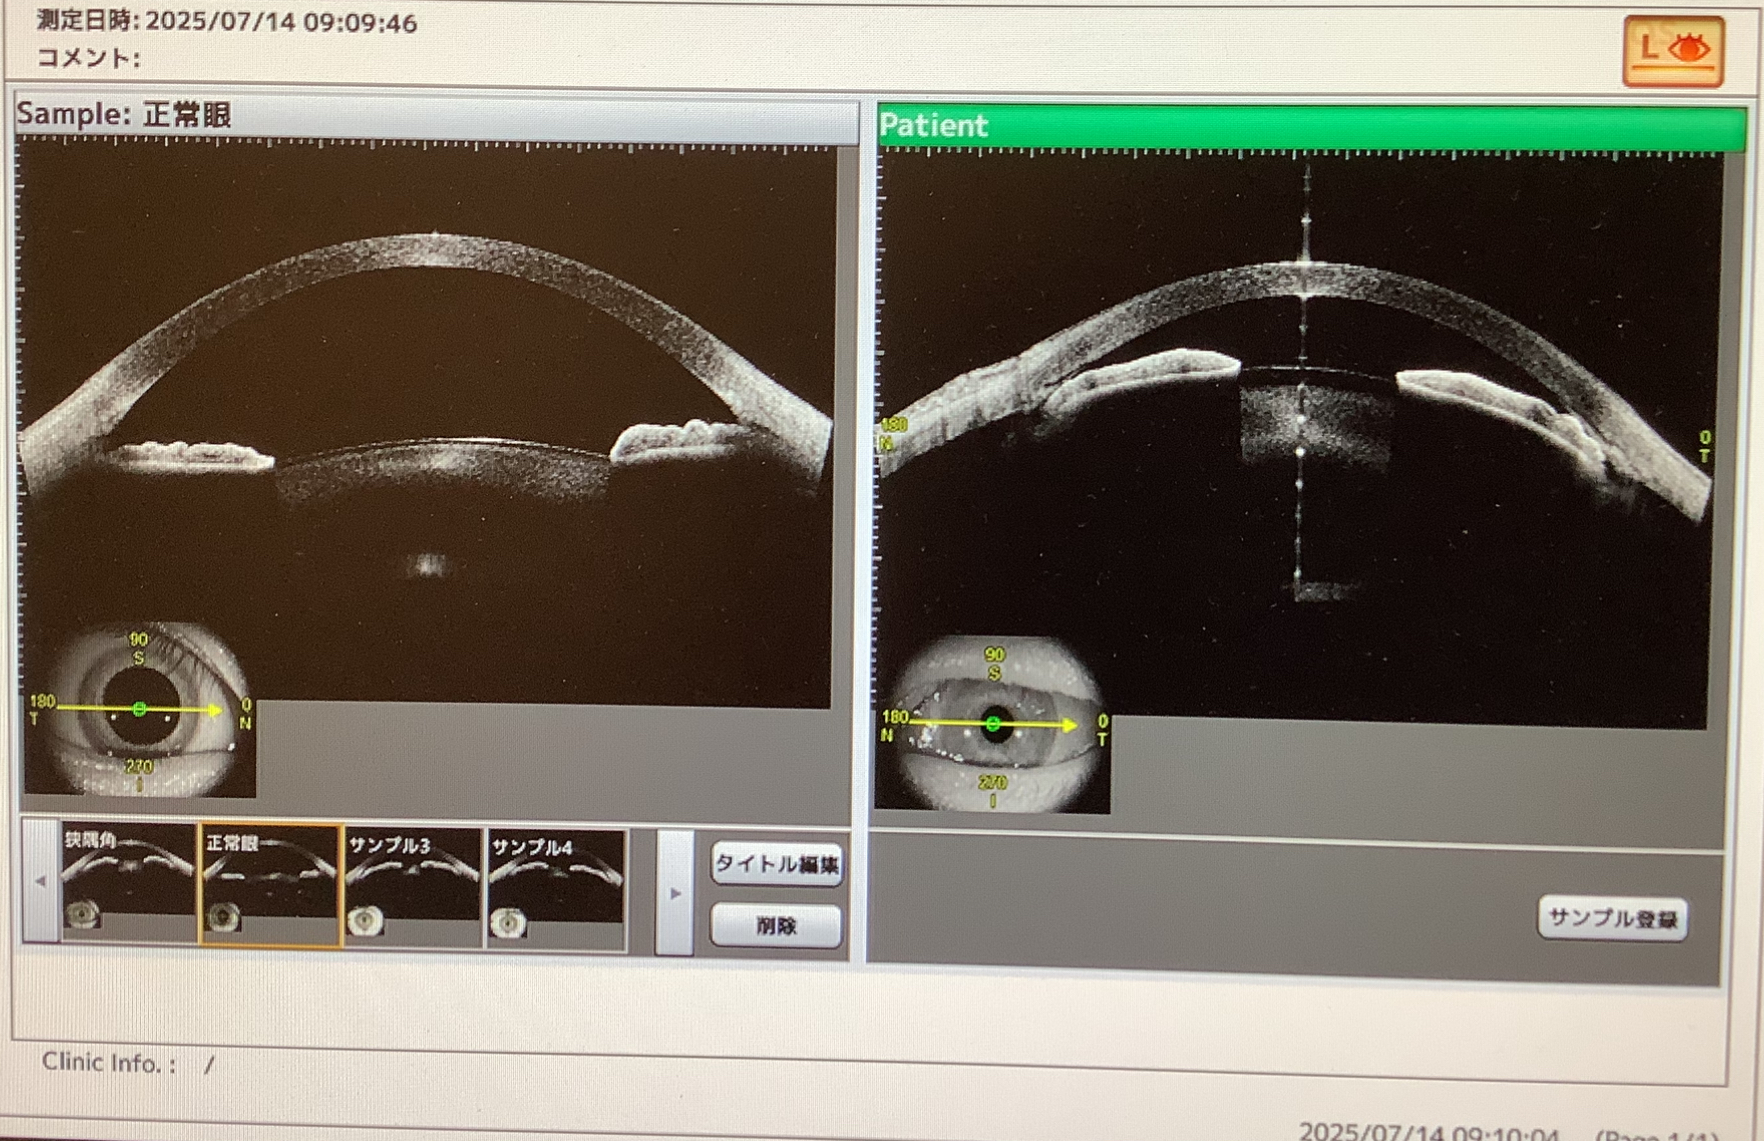

昨日の手術では、先月、見えにくさを自覚して他院を受診したところ、急性緑内障発作のリスクがあると白内障の手術を勧められたものの、『チン小帯が弱いから難しい手術になる』と言われ、先週、当院を受診され、結局、当院で手術を受けてくださった50代後半の男性の方の左眼の手術がありました。

この方は両眼とも前房が非常に浅く、左眼は眼圧も高く、緑内障発作を起こしかけているような眼で、昨日の手術でも確かにチン小帯が弱く、カプセルエキスパンダーという水晶体を支える補助器具を使っての手術となりました。20分弱とちょっと時間はかかりましたが、なんとか無事に白内障を取り除け、眼内レンズを入れて手術が終えられ、今日の診察でも経過良好でよかったです。